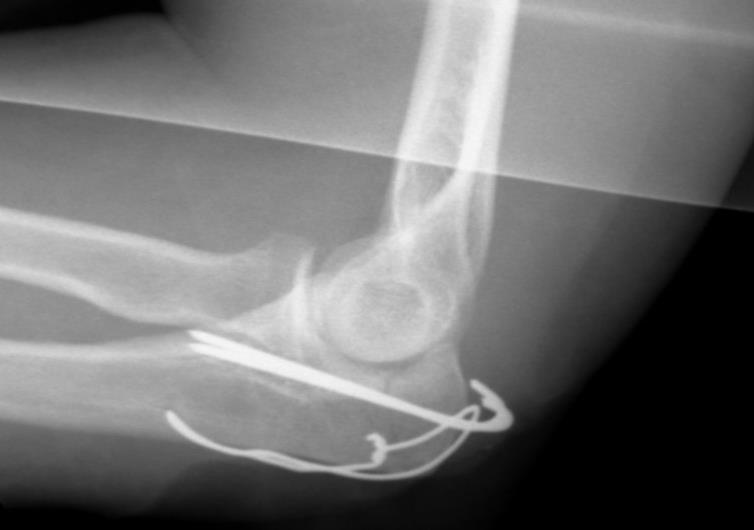

ELLBOGEN

Der Ellbogen [cubitus] setzt sich aus den Knochen des Ober- und Unterarms zusammen. Das Gelenk ist für Beugen, Strecken und Drehen verantwortlich. Zum Wenden und Drehen benötigt er das Radioulnargelenk.